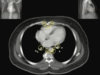

IMAGEN POR TAC

Imagen por TAC

Imagen por TAC

imagen por TAC

Imagen por TAC

In Figure 3.5.5 (at about the level of T2), the paratracheal and para-oesophageal nodes (50) are closely entwined. In this region, the deep axillary lymph nodes (48) can also be seen. Another common site for lymph node involvement from breast tumours, it can be seen that there is plenty of room for growth in the fatty spaces of the axilla. Anterior and medial to these are the interpectoral nodes (49). These are also known as ‘Rotter’s nodes’. The anterior mediastinal nodes (51) lie just posterior to the sternum.

In Figure 3.5.5 (at about the level of T2), the paratracheal and para-oesophageal nodes (50) are closely entwined. In this region, the deep axillary lymph nodes (48) can also be seen. Another common site for lymph node involvement from breast tumours, it can be seen that there is plenty of room for growth in the fatty spaces of the axilla. Anterior and medial to these are the interpectoral nodes (49). These are also known as ‘Rotter’s nodes’. The anterior mediastinal nodes (51) lie just posterior to the sternum.